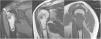

Reporte de casoSe trata de una mujer de 55 años que asistió a consulta externa por antecedente de 12 meses de dolor en el hombro derecho sin traumatismo previo. El dolor se asociaba con edema y la limitación funcional empeoraba al elevar la extremidad. En la exploración, el nivel de dolor era de 9/10 y aumentaba con la elevación y la flexión anterior. Las pruebas de Jobe y Yocum fueron positivas, pero sin inestabilidad articular. Presentaba abducción de 60°, flexión anterior de 65°, rotación externa de 10° y rotación interna completa. El puntaje QuickDash y American Shoulder and Elbow Surgeons Score (ASES) fueron 70,5 y 11,68, respectivamente. Las proyecciones radiográficas mostraron una extensa lesión intramedular compatible con un tumor encondromatoso localizado en el húmero proximal sin extensión a la cortical ósea ni presencia de fracturas (figura 1). La ecografía reveló, adicionalmente la presencia de tenosinovitis del supraespinoso. La resonancia magnética (RM) corroboró la presencia de un encondroma de gran tamaño, mostrando adicionalmente un desgarro completo y retracción del tendón del supraespinoso y tendinosis del infraespinoso (figura 2).

DiscusiónDescribimos un caso concomitante de encondroma de húmero proximal y ruptura del manguito rotador reparado con técnica artroscópica transósea sin anclajes en una mujer de 55 años. Tras un año de seguimiento, los resultados funcionales de la paciente sugieren que este procedimiento es una opción adecuada cuando existen dudas sobre la calidad ósea en la que se van a colocar los anclajes.Los encondromas son tumores cartilaginosos benignos que involucran la metáfisis-diáfisis de los huesos tubulares. Suelen ser asintomáticos y su descubrimiento es incidental en la mayoría de los casos1,2,18. Sin embargo, cuando se acompaña de dolor, si no hay signos evidentes de actividad tumoral, se debe considerar una lesión articular o tendinosa. Estudios previos han demostrado la ruptura del manguito rotador como una de las posibles causas de dolor de hombro en presencia de un encondroma del húmero proximal3–5. Levy et al.4 mostró que el dolor y la pérdida de rango de movimiento eran los síntomas de presentación más comunes en pacientes con encondroma de húmero proximal. En ese estudio, el síndrome de pinzamiento, la lesión del manguito rotador y la tendinitis fueron la fuente del dolor en hasta el 82% de los pacientes4. El caso de este reporte tuvo una presentación similar ya que la paciente inició con dolor en el hombro derecho y limitación funcional que aumentó con el tiempo y que finalmente la llevó a consultar a ortopedia. Además, aunque un encondroma era evidente en las radiografías simples, no explicaba el dolor crónico ni la pérdida de rango de movimiento. La RM confirmó una ruptura completa del tendón del supraespinoso y tendinosis del infraespinoso, lo que avala el abordaje sistemático que se debe seguir ante un caso como este y la importancia de la RM para establecer el diagnóstico definitivo2–4.